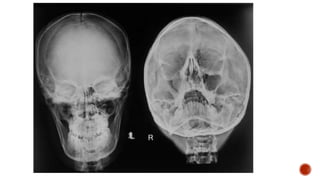

 AP and lateral radiographs of the skull show multiple tiny lucent areas with areas of

sclerosis in between, giving rise to salt and pepper skull appearance.

 Radiographs of both the legs, knees and left humerus show diffuse osteoporosis with

few well defined lytic areas.

 Radiograph of the hand shows osteoporosis with coarse trabeculations of the

phalanges with mild erosions along tteh radial aspect.

HYPERPARATHYROIDISM

FINDINGS

 Osteopenia

 Subperiosteal resorption: classically along radial aspects of phalanges

 Floating tooth

 Subchondral resorption (lateral end of clavicles, pubic symphysis, sacroiliac joints)

 Subligamentous resorption(ischial tuberosity, trochanters)

 Brown tumors(more common in primary)

 Salt and pepper skull

 Rugger jersey spine

 Secondary and tertiary hyperparathyroidism may be associated with osteosclerosis of

renal osteodystrophy and osteomalacia of vitamin D deficiency

 Superior and inferior rib notching may be seen